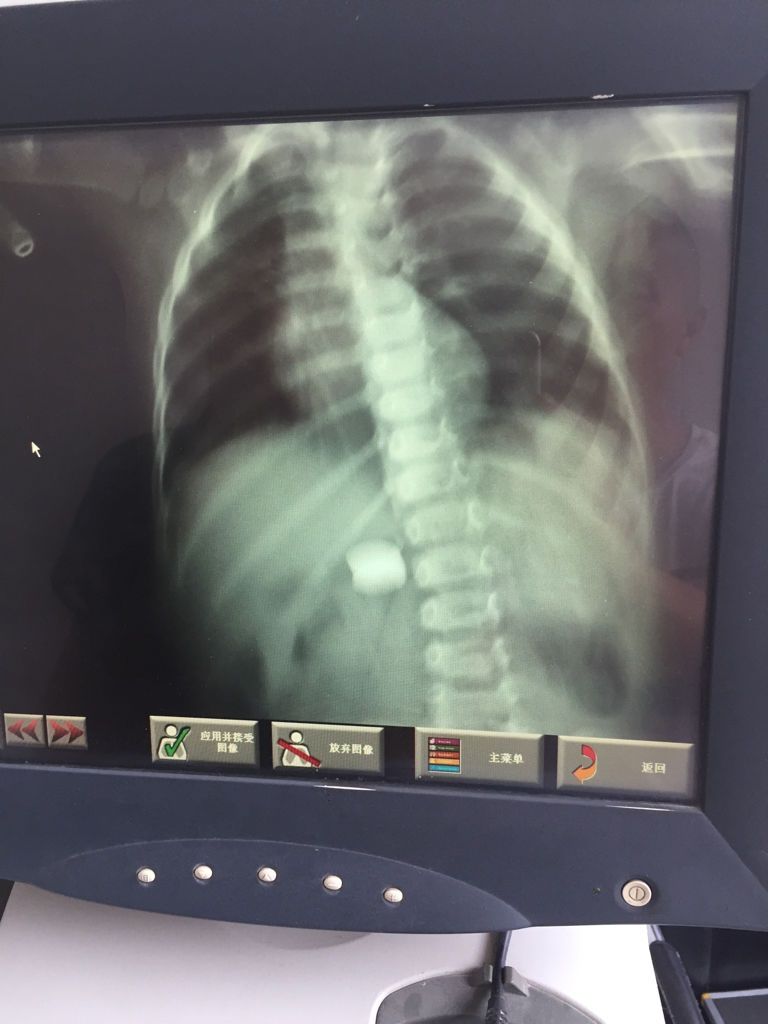

2岁孩子误食一毛钱硬币这是在什么位置啊?? 点击展开 匿名用户 2016-07-21 22:21 满意回答 孩抓最子二岁了,有误食硬币的现象,如果没有卡到,一般不要紧,会患崭耻随大便排出的,多吃水果孟法蔬菜比较好的观察. 匿名用户 2016-07-21 22:22 宝宝知道提示您:回答为网友贡献,仅供参考。 相关问题 一岁半宝宝误食一毛钱硬币,立刻去医院拍了腹平片,结果大夫说 一毛钱硬币大小的红斑,是婴儿湿疹吗?怎么处理 宝宝后背有四块像一毛钱硬币那么大的点是怎么回事